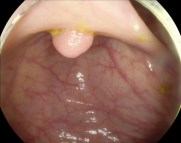

Vision foundation models like the Segment Anything Model (SAM), pretrained on large-scale natural image datasets, often struggle in medical image segmentation due to a lack of domain-specific adaptation. In clinical practice, fine-tuning such models efficiently for medical downstream tasks with minimal resource demands, while maintaining strong performance, is challenging. To address these issues, we propose BALR-SAM, a boundary-aware low-rank adaptation framework that enhances SAM for medical imaging. It combines three tailored components: (1) a Complementary Detail Enhancement Network (CDEN) using depthwise separable convolutions and multi-scale fusion to capture boundary-sensitive features essential for accurate segmentation; (2) low-rank adapters integrated into SAM's Vision Transformer blocks to optimize feature representation and attention for medical contexts, while simultaneously significantly reducing the parameter space; and (3) a low-rank tensor attention mechanism in the mask decoder, cutting memory usage by 75% and boosting inference speed. Experiments on standard medical segmentation datasets show that BALR-SAM, without requiring prompts, outperforms several state-of-the-art (SOTA) methods, including fully fine-tuned MedSAM, while updating just 1.8% (11.7M) of its parameters.